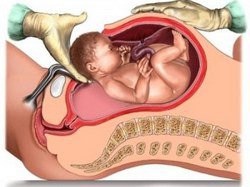

Все більше жінок фізично за станом здоров'я не можуть народити здорову дитину самостійно. Тому при наявності таких проблем, як вузький таз або неправильне прикріплення плаценти до матки (по-медичному це називається передлежанням плаценти), робити кесарів розтин - це єдиний шанс народити. Крім того, лікарі наполягають на такій операції, якщо мама має, хоча б одне з цих захворювань - ВІЛ, генітальний герпес в гострій формі, порок серця, діабет. Також показано кесарів розтин при наявності пухлини в області шийки матки. Іноді такі пологи рекомендують, якщо вагітність наступила в результаті штучного запліднення або ж існує ймовірність розриву матки через попередні операції. Але буває і так, що кесарів розтин потрібно проводити вже в процесі народження дитини. Такі фактори, як відсутність родової діяльності, сильна кровотеча, гіпоксія плода - все це вимагає негайного хірургічного втручання. Деякі жінки ще одним аргументом «за» кесарів розтин назвуть відсутність болю. Але це більш ніж умовний аргумент, адже біль буде пізніше, до того ж занадто багато ризику для матері і дитини, якщо проводити таку операцію без медичних показань. Подумайте самі, вам розрізають живіт і звідти витягають малюка, а потім накладають шви, які довго гояться.

Отже, плавно, ми переходимо до аргументів «проти» кесаревого розтину. В першу чергу звернемо увагу на ризик для крихти. При кесаревому розтині жінці вводять дозу наркозу, і дитина також її отримує. Крім того, малюк піддається великому ризику в плані здоров'я. Наприклад, можливі ускладнення в дихальній системі маленького організму. До речі, такий ризик трохи знижується, якщо операцію проводити після 39-го тижня вагітності. На досвіді наших близьких знаємо, що не завжди точно можна вирахувати дату народження, тому заздалегідь плануючи операцію, зберігається ризик народження недоношеного малюка з усіма витікаючими наслідками. Ще один мінус для дитини, якщо вона з'явилась на світ після кесаревого розтину, то, що вона може бути з матір'ю тільки на другу-третю добу, тоді ж мати і може прикладати малюка вперше до грудей. Все це ускладнює природний контакт мами і крихти. Що стосується можливих ризиків для самої жінки, то тут не менш важливі нюанси. Наприклад, той же наркоз серйозно впливає на організм матері. Так само, як ми вже відзначали, післяопераційна адаптація проходить дуже складно. Під час операції зберігається ризик важких ускладнень - від крововтрати до пошкоджень внутрішніх органів (кишківника та сечового міхура).